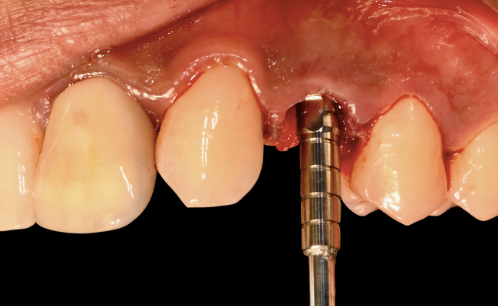

Step 5 — Guided drilling and implant placement. On the day of surgery, UL3 was extracted. The tooth-supported surgical guide was seated on the adjacent teeth and its fit verified. The SMOP guide design left the surgical site fully visible — giving the clinician direct sight of the osteotomy while still controlling the drill angle and depth.

Guided drilling sequence — initial pilot drill through the surgical guide Guided drilling sequence — progressive osteotomy widening

Drilling sequences The osteotomy followed the guided path precisely. Full visibility of the site and controlled cooling throughout.

A Thommen ELEMENT RC implant (4.0 mm diameter, 11 mm length) with Inicell superhydrophilic surface was placed. The final 3D position matched the pre-operative plan exactly.